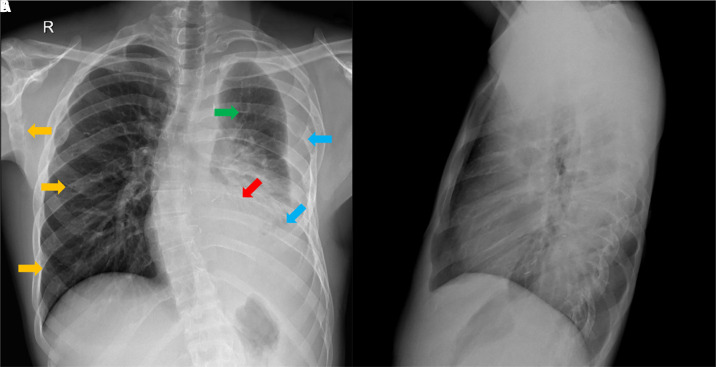

Case presentation: We present a case of a 19-year-old male with Gorham-Stout disease, multiple cervical lymphangiomas, and several thoracic complications successfully treated with sirolimus.

Abstract Image